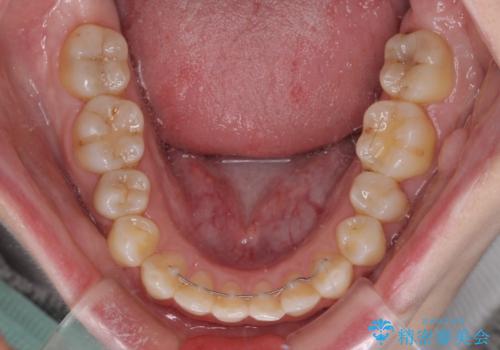

前歯のデコボコを改善 目立たないワイヤー矯正

- 前歯のデコボコを気にして来院された患者様です。

下顎が骨格的にずれており、上下正中を合わせることは難しいことが予想されたため、デコボコの解消を主目的として、ワイヤー矯正を行うこととしました。